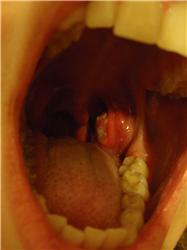

Pro větší náhled klikněte na obrázek

Chcela by som sa opýtať. Mám už od dvanástich rokov problém s mandľami a to taký že si z nich už od tohto veku neustále večer musím vybrať kusy hnisu, z trochu napuchnutých mandlí. Bola som s tým u doktora a ten mi oznámil, že mám chronický zápal mandlí a že sa mi neustále tvoria hnisavé čapy, ale že vyberať ich netreba. Pred pár dňami mi ale mandľa z ničoho nič napuchla do polovice hrdla a je cela pokrytá hnisom, ktorý už vybrať nejde. Vyberú mi ju teraz? Za akú dobu sa v takomto prípade koná operácia od kontroly lekárom keď je to takto akútne? Da sa vybrať len jedna mandľa, pretože s druhou problém nemám. Veľmi ďakujem za odpoveď.